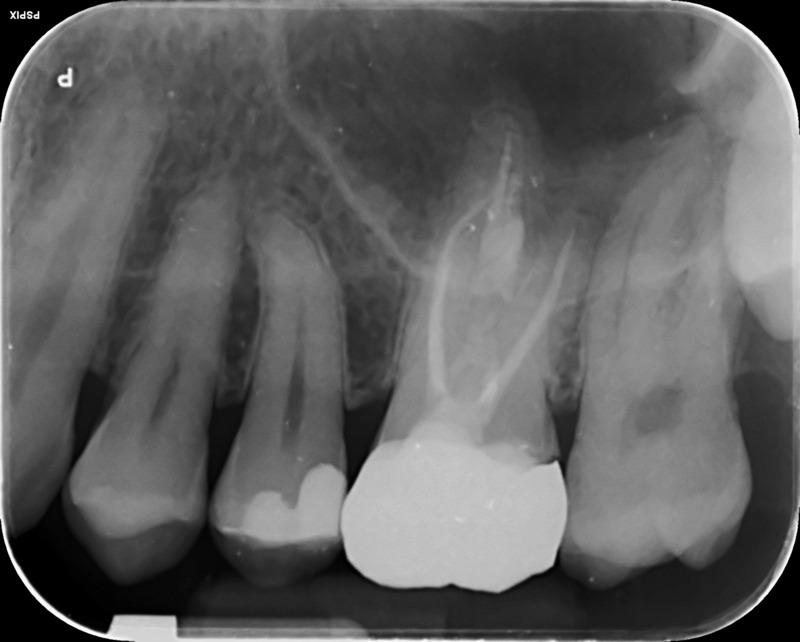

Multi-disciplinary: root canal treatment, molar apicectomy and bone regeneration

Pre-operative X-ray

Post-operative X-ray